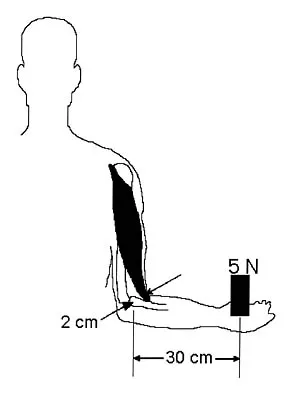

Question 41

Which of the following structures runs through the site indicated by the arrow in Figure 11?

Explanation